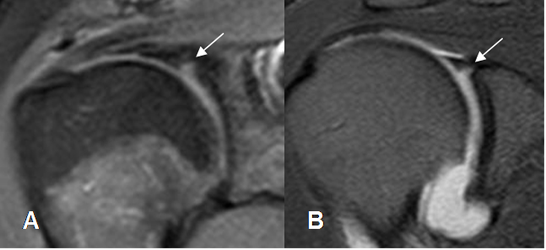

Fig 75. Lesión SLAP.

A: RM coronal en T1 y B: RM coronal en STIR. Imagen hiperintensa y en sentido transverso sobre el labrum superior, por lesión SLAP.